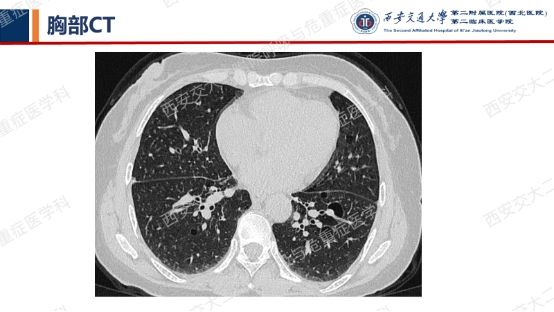

患者呼吸道症状并无太多特异性,还是从影像资料入手,右肺中叶外侧段高密度灶并纵隔及右肺门淋巴结肿大,同时存在双肺多发囊性病变,一元论?多元论?

囊性病变常要鉴别的疾病包括我们第一期的BHDLAM,还有LIP(淋巴细胞性间质性肺炎)、PLCH(肺朗格汉斯组织细胞增多症)、PLCDD(肺轻链沉积病)等。该患者囊性病变特点:沿支气管血管束周围分布,多个囊有血管贴边或穿行于囊肿壁。追问患者有口干不适,进一步行SS-A 52 101.65 AUSS-A 60 47.30AUANA 阳性(+),滴度1:10000 阳性(+),又经唾液流率、泪液流率、唇腺活检及风湿免疫科会诊,诊断干燥综合征。

需要强调的是,LIP影像表现较为复杂——弥漫性GGO+边界模糊之小叶中心性结节+胸膜下结节+支气管血管束增粗+多发囊样气腔各种征象可单独或同时存在。我们最近几期病例会聚焦在弥漫性囊性肺疾病,所以展示的病例影像基本以囊变为主。

第一期埋下的伏笔,以下2例不同患者的胸部影像改变,又分别考虑什么疾病呢?答案呼之欲出,相信大家也越来越清晰了!